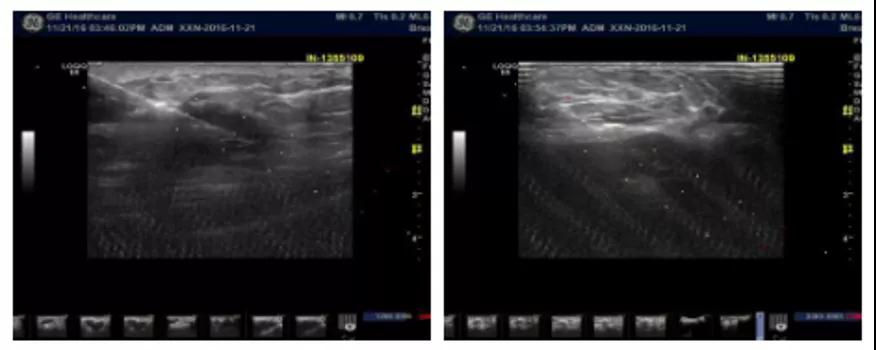

乳腺B超(当地)检查示:右乳实质样团块病灶(BI-RADS-4c级),考虑乳腺癌,右侧腋窝下淋巴结肿大,部分结构已改变。

2016-11-22在超声引导下行“右侧乳腺肿物及腋窝淋巴结穿刺活检术”。

2018-3-5复查B超示:右卵巢内可见约1.6cm×1.5cm无回声区,内可见大小约3.0cm×2.3cm低回声团,子宫左后方可见约6.3cmx3.9cm不均质回声团,边界清,形态欠规则,可见血流信号。